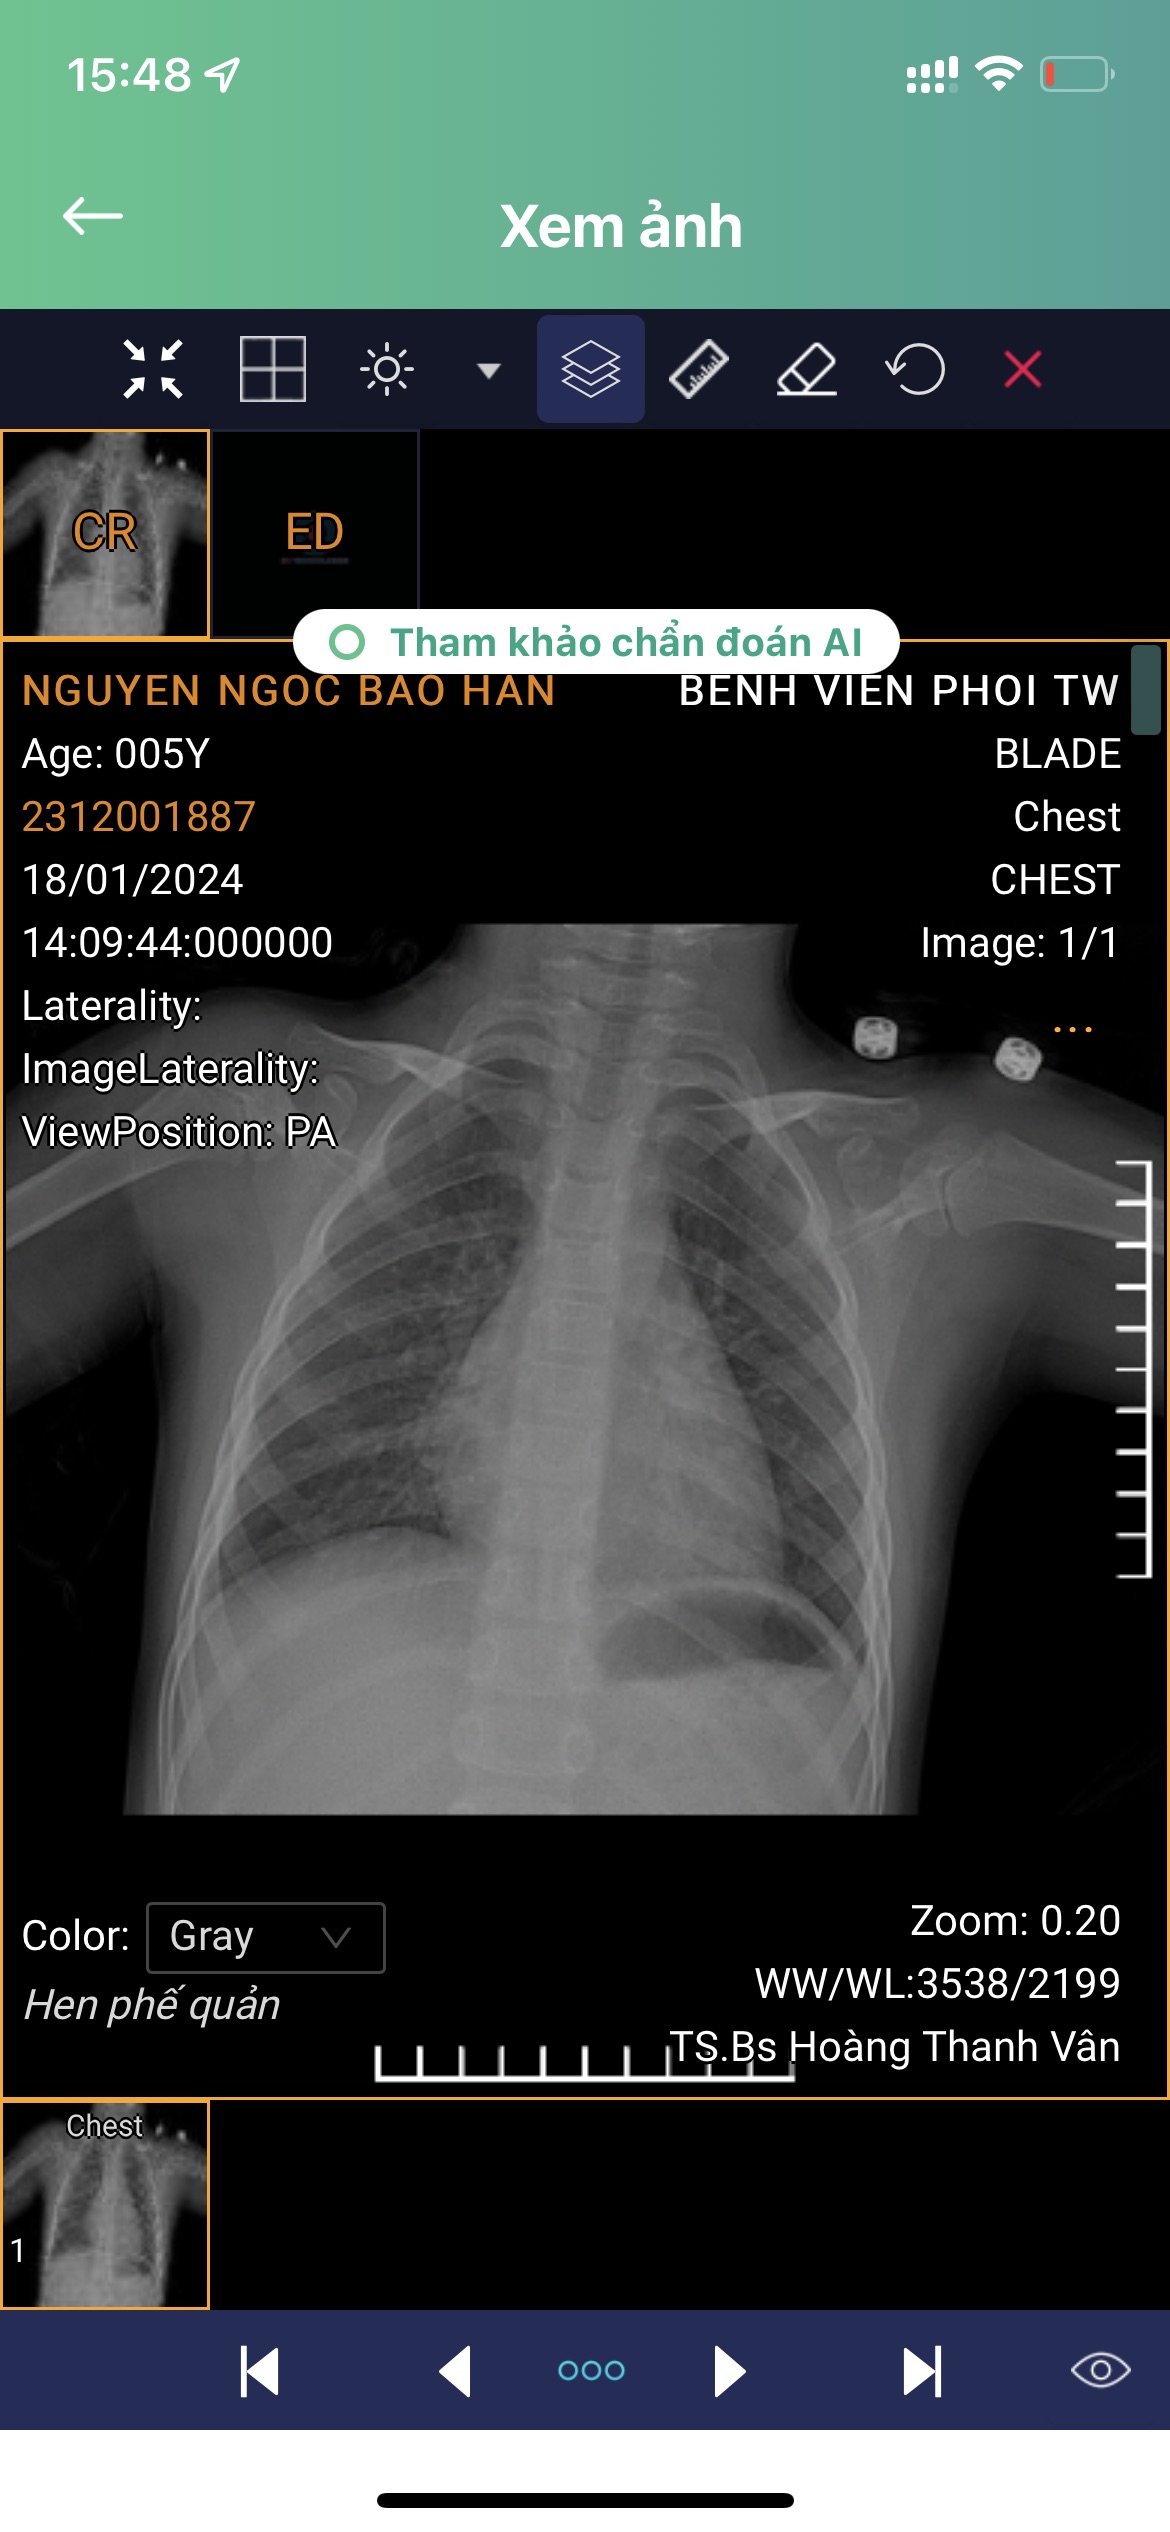

Cho em hỏi phim xquang này cho thấy phế quản và phổi có bị làm sao không ạ